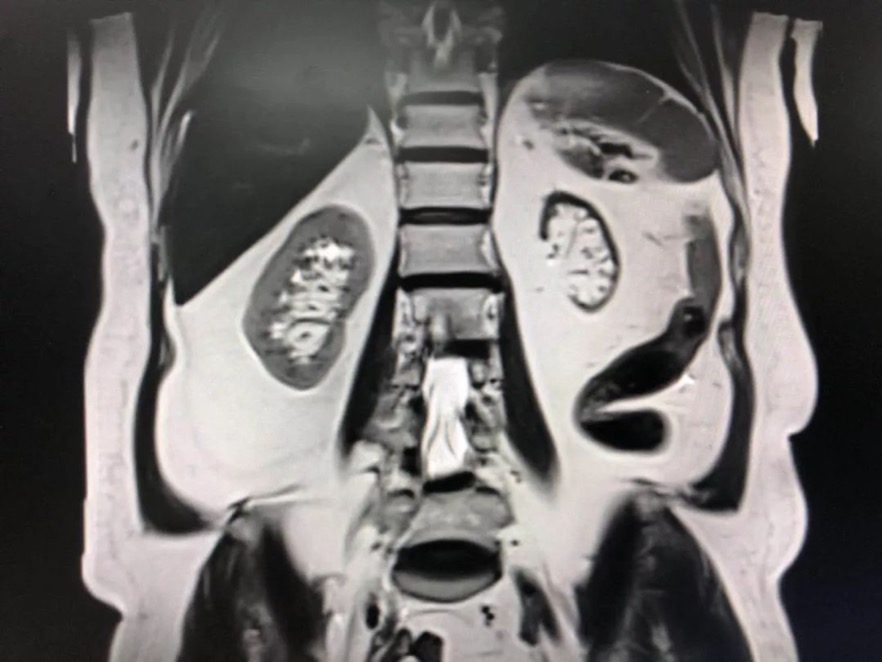

在住院后的检查中,曹女士又被发现血肌酐296μmoI/L(女性的血肌酐正常范围为44~97μmoI/L),尿素20.4mmol/L(正常范围为2.0-7.1mmol/L),高出正常范围很多。医生询问得知,八年前曹女士就被发现左肾萎缩,并患有慢性肾功能不全。

曹女士现在只剩一个肾在工作。若进行介入手术,含碘的造影剂随时可能加重肾功能恶化,引发急性肾衰竭和尿毒症。即便两项手术都成功也会严重影响生活质量。若不手术,曹女士的腹主动脉瘤是个“定时炸弹”,随时可能破裂,而且心脏血管也随时可能梗塞,直接危及生命。

手术开始后,陈岩借助血管内超声,发现患者曹女士的右冠状动脉迂回曲折,而且还有一定程度的钙化,在正常的冠状动脉介入手术中也属于难度大、风险高的类型。因为使用血管内超声看到的是进行中的情况,实际手术时可能又发生了变化。脱离了造影影像的介入手术,对手术医生的操作技术和手术经验有极高的要求。